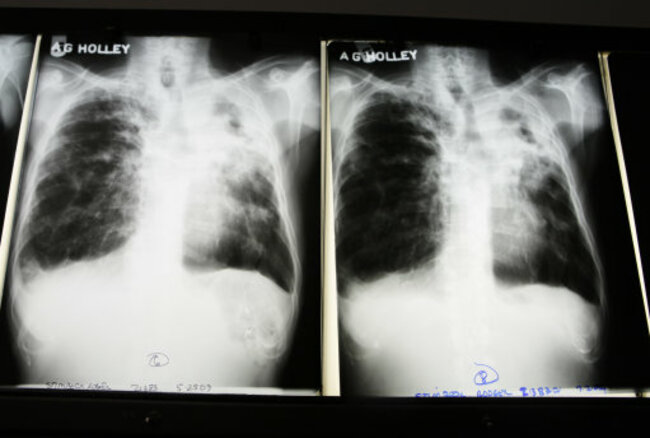

SCREENING FOR TUBERCULOSIS has begun at St Finbarr’s Hospital in Co Cork for hundreds of children and adults today, following an outbreak.

Over 220 people will undergo emergency tests to detect the disease, after three children at the Ballintemple National School tested positive for TB in the past three weeks.

O’Sullivan outlined the screening process, saying that people would be given an survey to complete, followed by a Mantoux skin test, and – if necessary – a chest X-Ray.